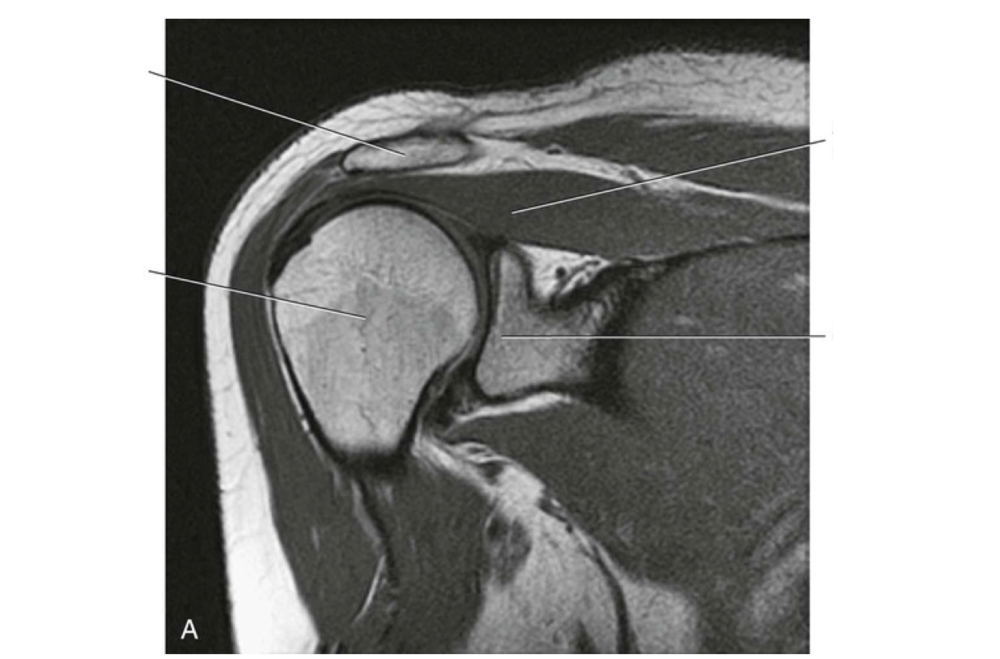

Question 6

Question

Label the image

Image:

187757d5-122c-4789-a0b2-7af3c3868335 (image/png)

Answer

clavicle

humerus

supraspinatus muscle

glenoid process